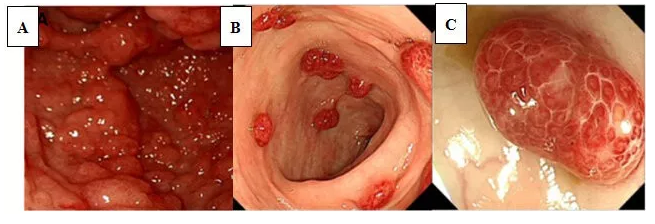

图1 FAP患者胃肠道内多发的息肉性病变